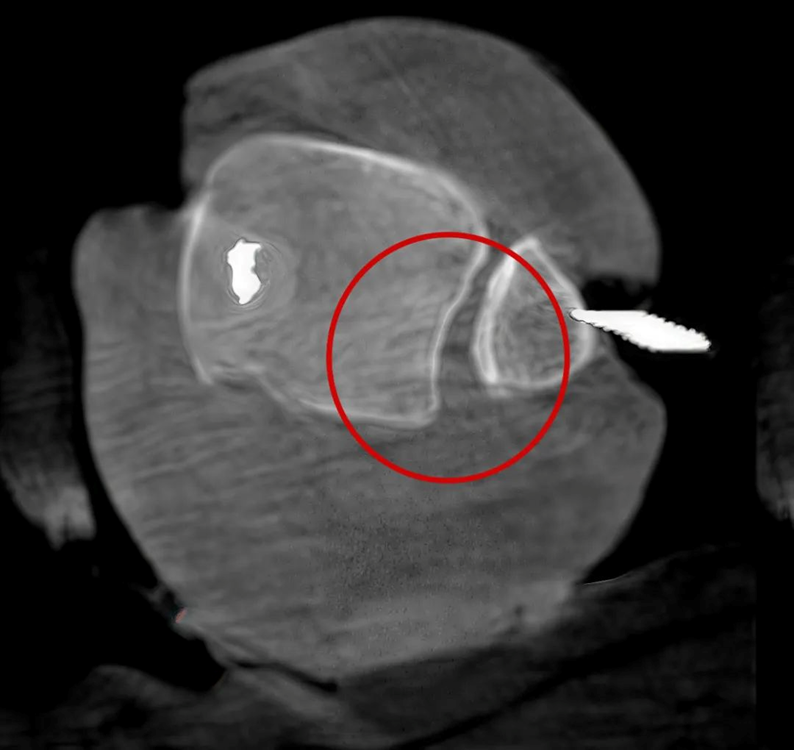

Case 2: Ankle Fracture Reduction (31 years old)

In ankle fracture reduction surgery, the reduction of the fracture site can be better visualized with 3D C-arm.

Good reduction of the tibiofibular syndesmosis on the AP and lateral views

3D imaging shows suboptimal reduction with inadequate congruency.